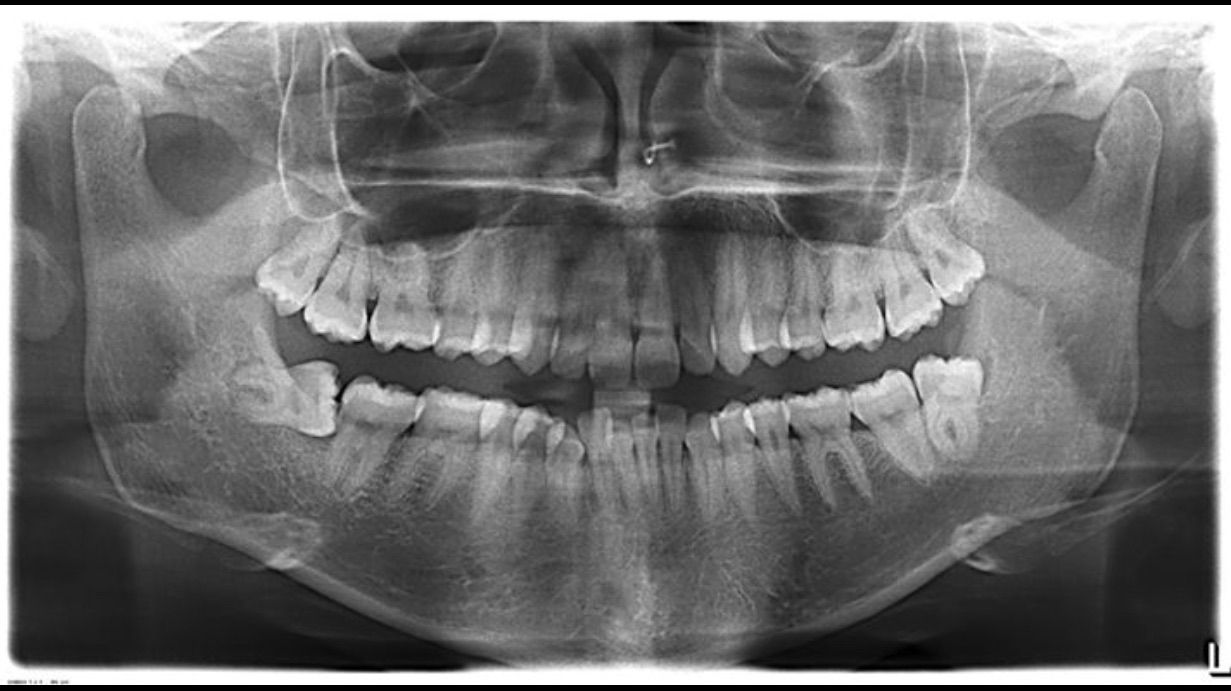

Ortopantomografia eseguita dopo l'estrazione dei quattro denti del giudizio